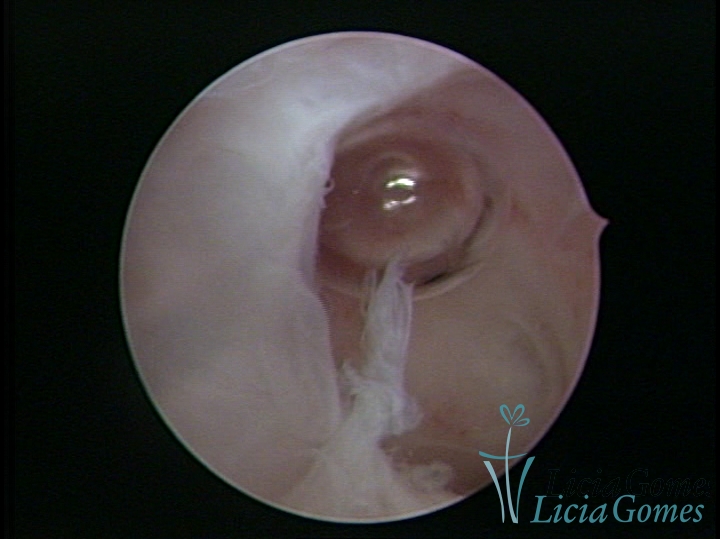

Sinéquia TIPO FIBROSA

As Sinéquia uterinas são cicatrizes (aderências) entre as superfícies das paredes uterinas, que podem ocorrer após manipulação cirúrgica, ou curetagem uterina, ou após um processo inflamatório na cavidade uterina (endometrite), podendo levar a alterações menstruais, infertilidade, e complicações obstétricas, como abortamento, parto prematuro.